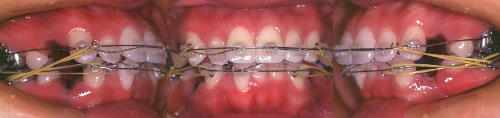

写真4 ワイヤーを装着して歯並びを矯正している、治療中の口腔内写真。

写真5 前突が徐々に矯正され定着し始めているところ。